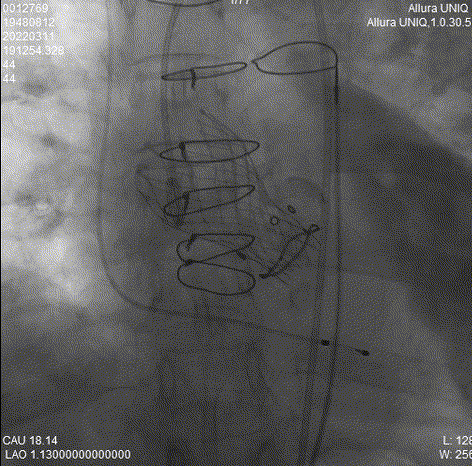

球囊后扩

瓣膜最终形态

术后造影及经食道超声探查未见瓣周漏,人工瓣膜无明显返流,跨瓣压差术前100mmHg,术后降为10mmHg,术中及术后未出现相关并发症,手术圆满完成。